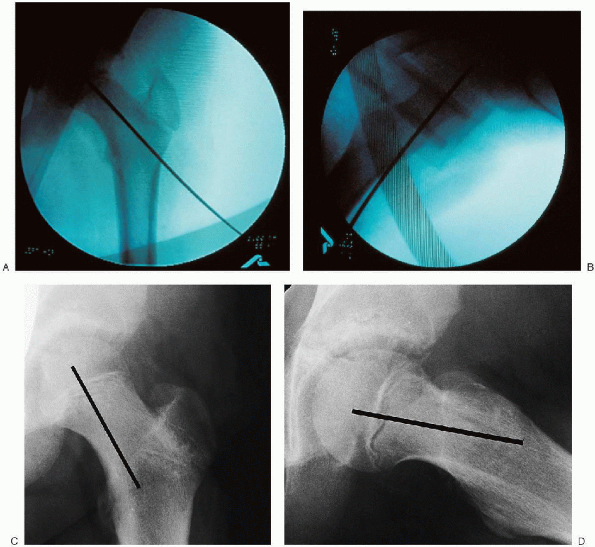

![]() |

FIGURE 24-3. Image intensifier in the anteroposterior plane (A) and resultant image (B). Image intensifier in the lateral plane (C) and the image obtained (D).

is imperative that the image intensifier be positioned and images taken

before proceeding with the surgery. Good images of the hip are needed

in the anteroposterior and lateral planes. The physis and outline of

the femoral head must be distinctly visualized to place the pin

properly and avoid penetration of the joint. It should be possible to

obtain views in both planes by rotating the arm of the image intensifier (Fig. 24-3).